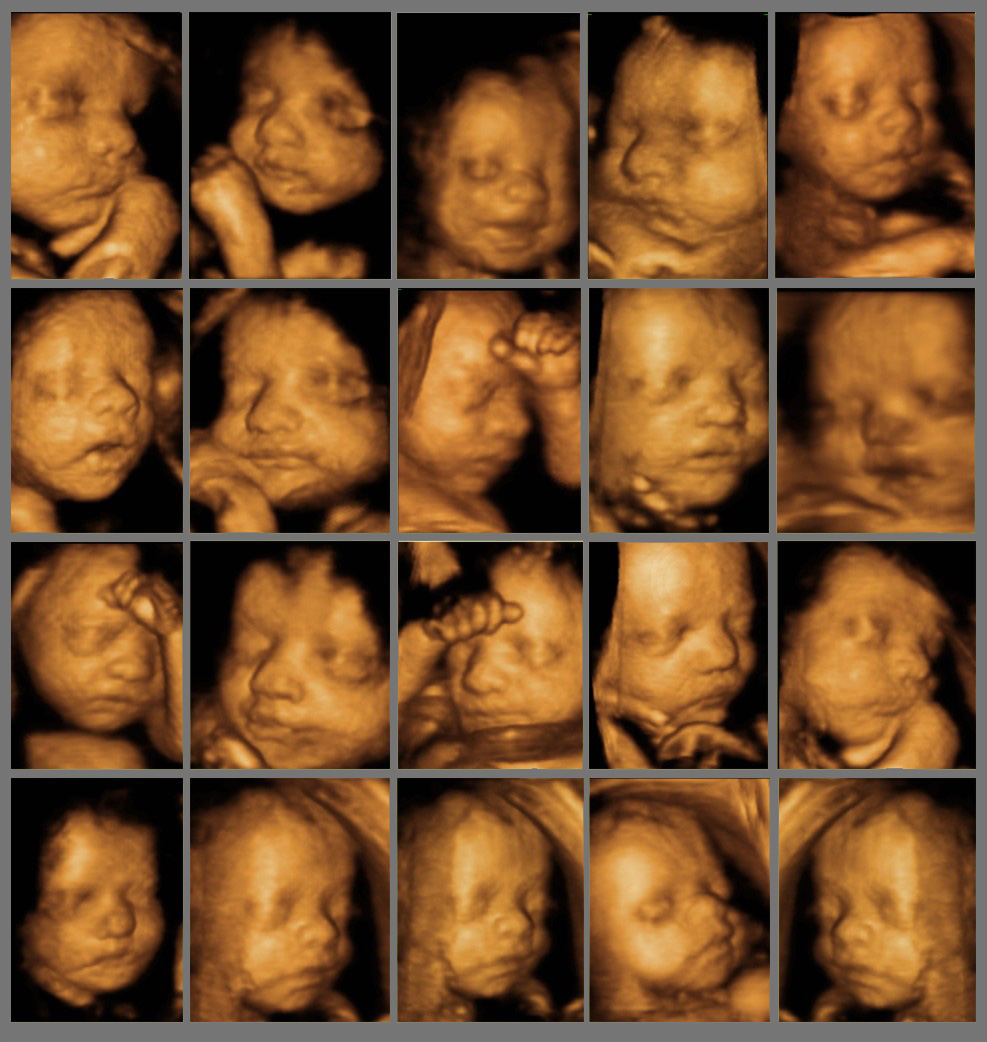

Fetal ekokardiyografi (Fetal Eko) ne zaman (hangi gebelik haftasında) yapılmalıdır ? Anne karnınd ...